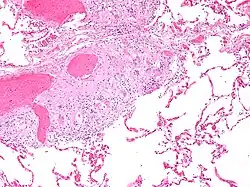

![]() Mikrofotografie znázorňující plicní sarkoidózu | |

Sarkoidóza, či též Besnierova-Boeckova choroba, je multisystémové granulomatózní zánětlivé onemocnění nejasného původu (etiologie). Jedná se o autoimunitní onemocnění, projevující se hlavně u dospělých v mladém a středním věku (častěji u žen, nekuřaček). Nemoc se v počátku často projevuje postižením a zvětšením nitrohrudních uzlin (známé jako bilaterální hilová lymfadenopatie, BHL), plicní infiltrací a postižením dalších orgánů (hlavně kůže a očí, dále též postihuje kosti, játra, srdce, ledviny, slinivka, atd).[1]